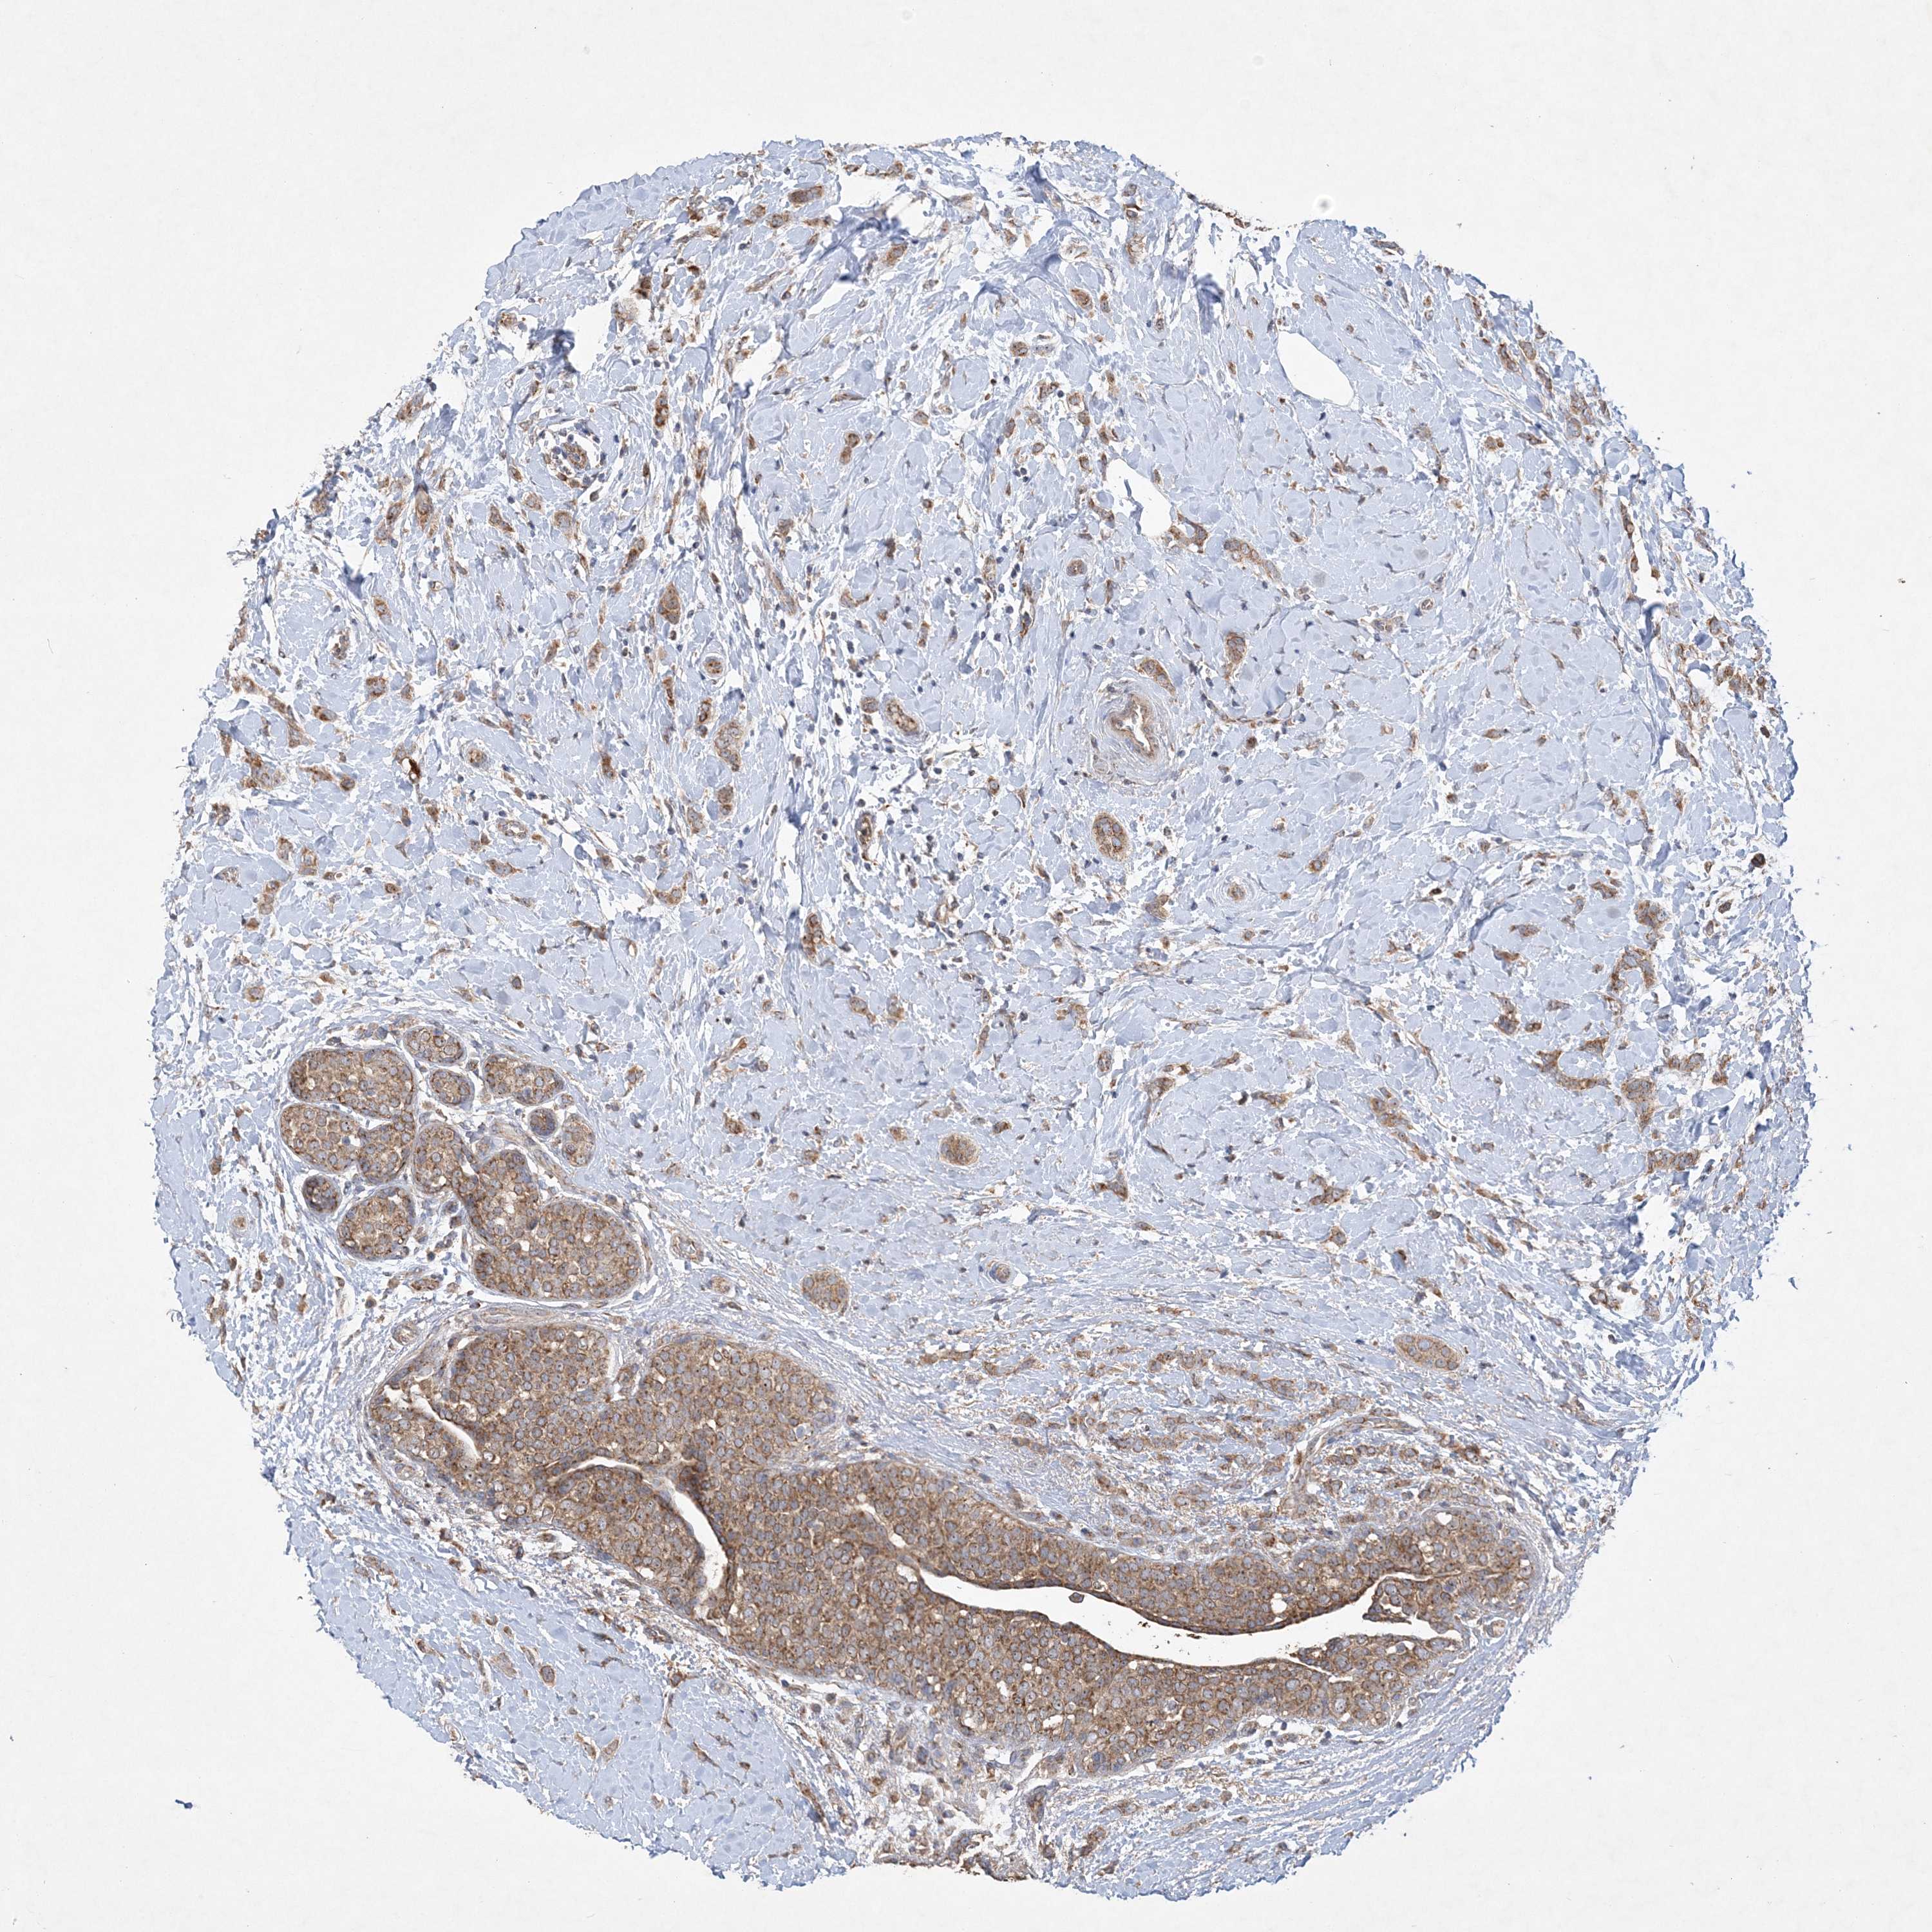

BRCA TCGA BRCA VALIDATION PROTEIN EXPRESSION

Breast cancer

Breast invasive carcinoma